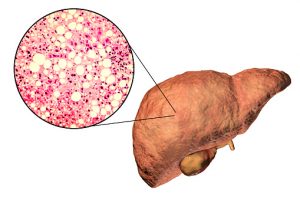

Fatty liver disease is a rising disease in America. As fat permeates the liver, it makes it sick and reduces its ability to function. If left untreated, fatty liver disease can progress into cirrhosis, which is irreversible and requires a liver transplant to treat.